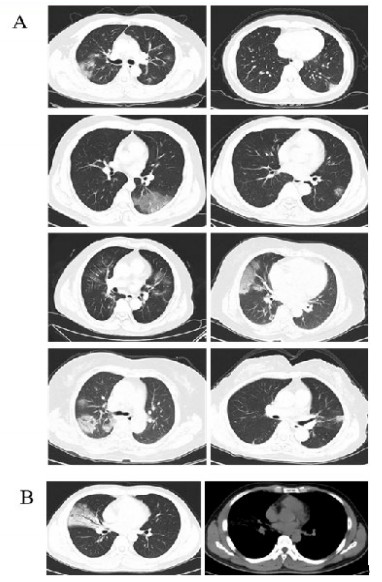

新型冠状病毒感染组患者胸部CT均有肺炎表现,其中8例为磨玻璃影,1例为实变影,见表 3和图 1。非新型冠状病毒感染组中有21例患者胸部CT正常。本研究所筛查的46例患者中,胸部CT正常者的新型冠状病毒核酸检测均阴性。

| A:8例患者在就诊时胸部CT可见磨玻璃影;B:1例患者就诊时胸部CT表现为实变影 图 1 新型冠状病毒感染患者胸部CT表现 Fig 1 The image characteristics of novel coronavirus infection patients |